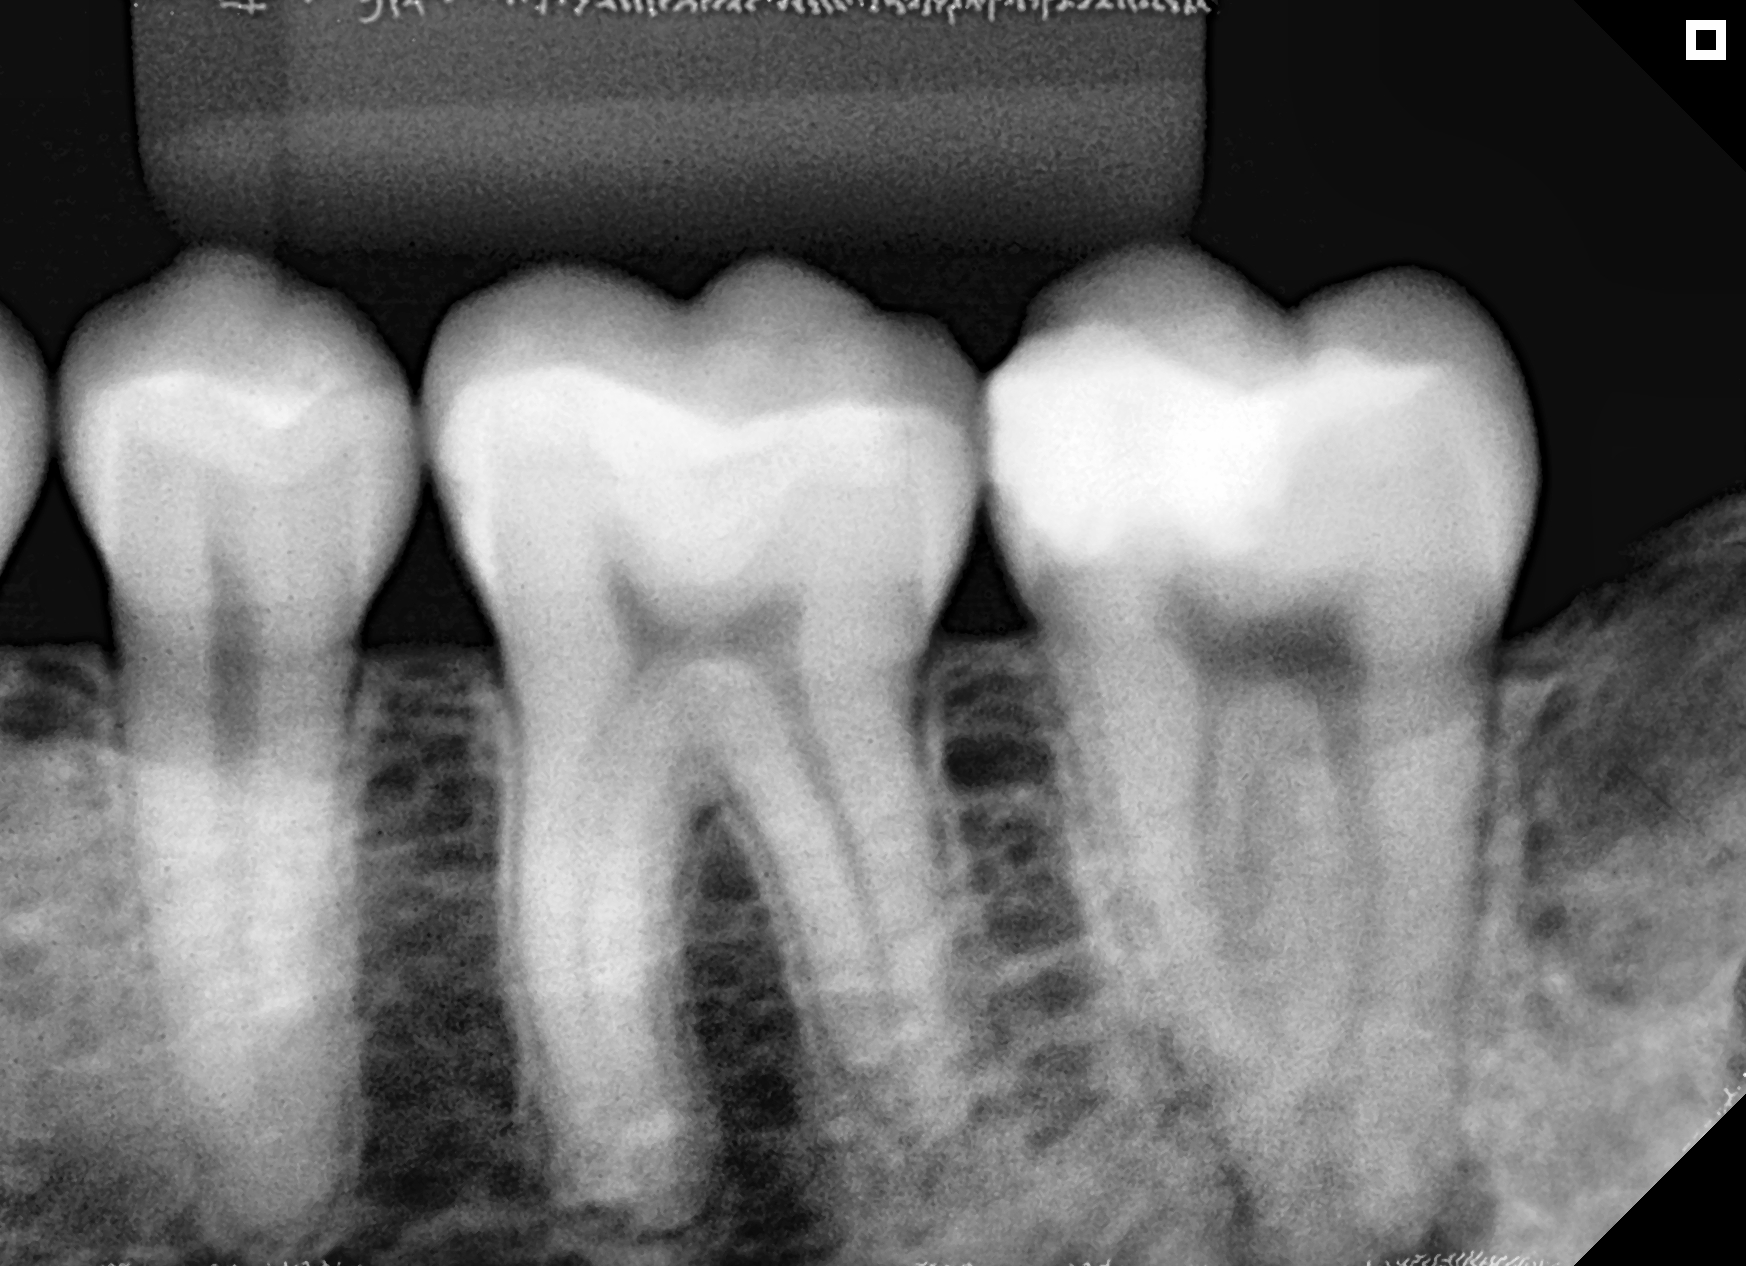

Microscópio e Raio-X Portátil. Equipamentos de última geração e técnicas avançadas para resultados excepcionais e seguros.

Resultados reais com tratamentos personalizados.

Antes

Depois